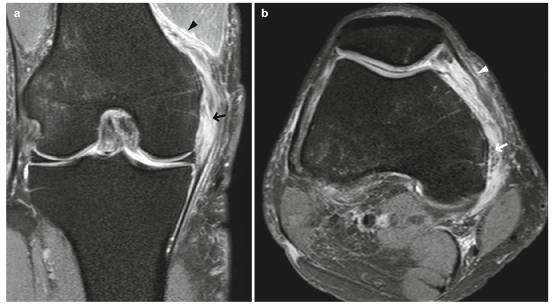

在2-3级MCL撕裂中,将会看到由于水肿和血肿导致的纤维不连续和信号异常(图5.8和5.9)。

- 水肿的变化可能不仅限于MCL本身,还可能扩展到周围的内侧支持带和股内侧肌(图5.8)。

图5.8的2级撕裂(部分撕裂)。一个40多岁的男性。(a)冠状面和(b)轴位FS PDWI显示MCL表层水肿肿胀和不连续(箭头)。水肿的改变也可见于内侧支持带(b中箭头)和股内侧肌(a 中箭头箭头)